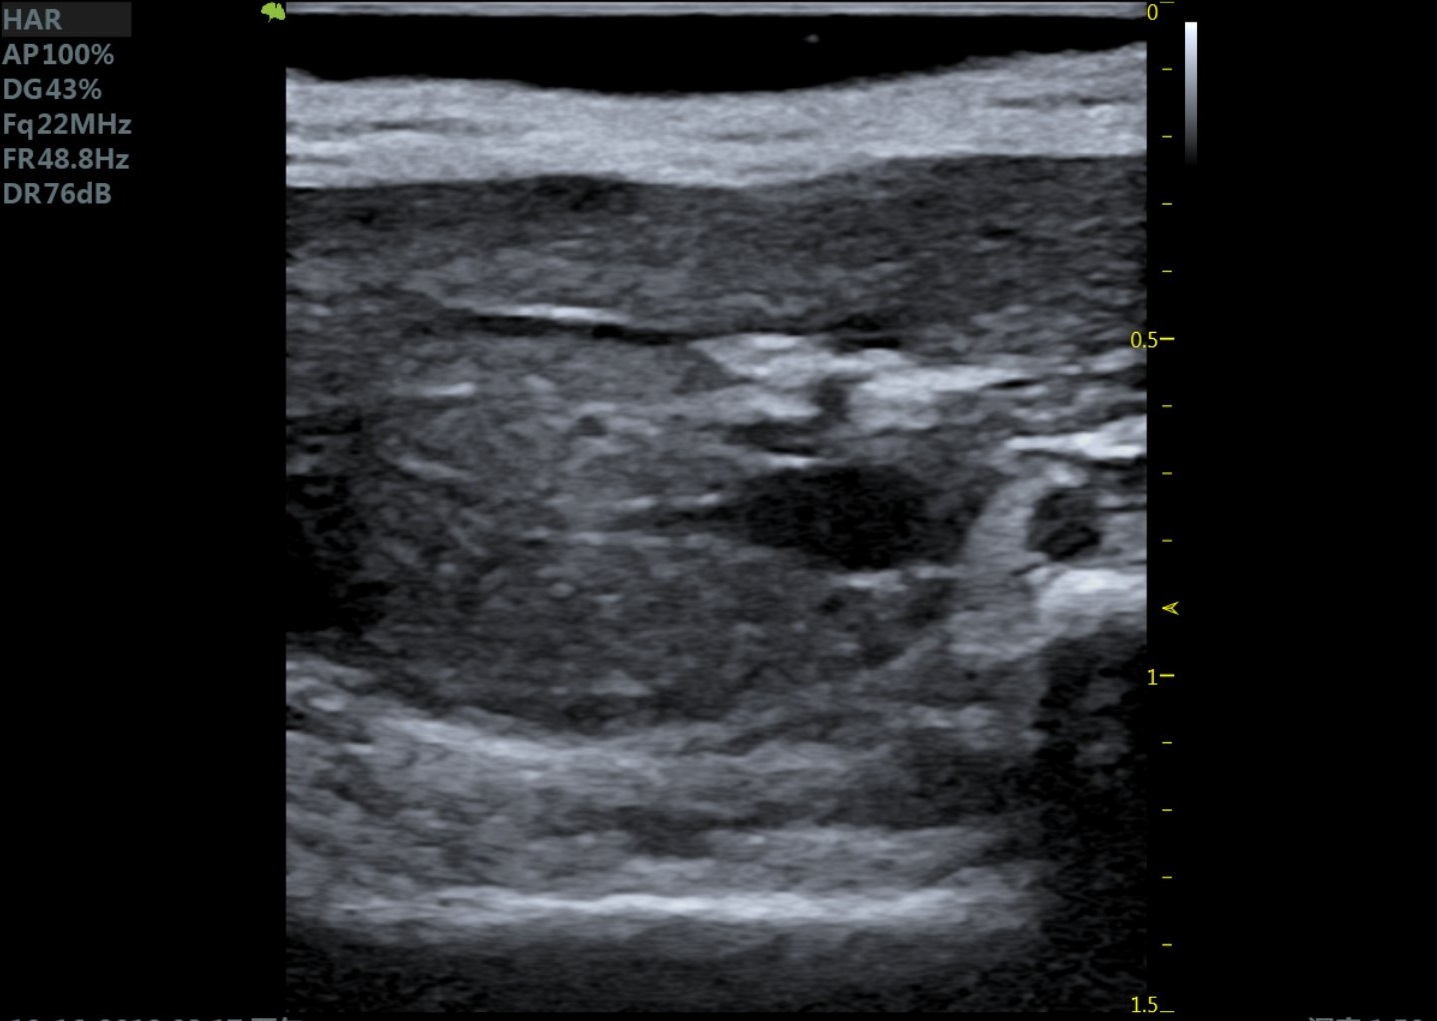

大鼠肝脏 大鼠肾脏